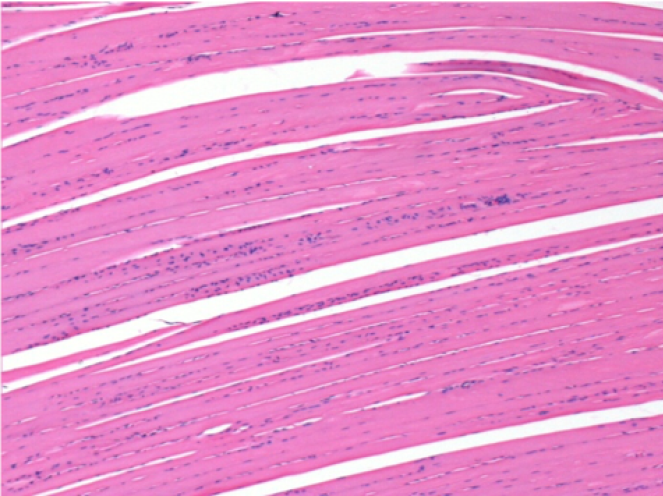

Через 1 місяць після ін'єкції Ендопілу 0,1 мл у правий претибіальний м'яз.

Те, що видно на знімках чорним кольором, не є некрозом, як можуть собі уявити деякі науковці!

Насправді, слід взяти до уваги 4 висновки

Через 3 місяці (90 днів) після ін'єкції Ендопіл 0,1 мл в правий претибіальний м'яз.